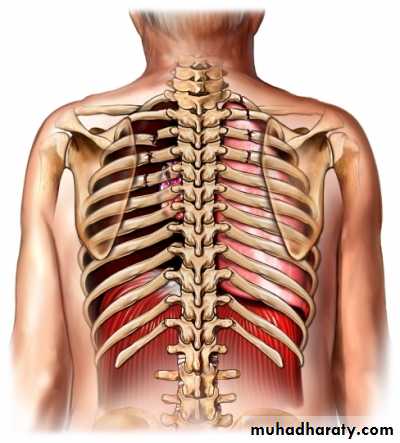

DEFINITION

A spontaneous pneumothorax (SP) is defined as the accumulation of air into the pleural space, collapsing the lung. This can be primary SP (i.e., without any obvious underlying lung disease) or secondary SP (i.e., with underlying lung disease).